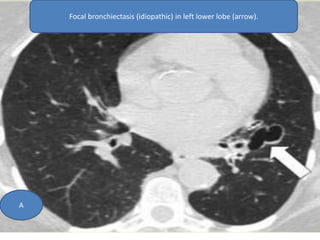

Focal bronchiectasis (idiopathic) in left lower lobe (arrow).

A

Focal bronchiectasis (idiopathic)in left lower lobe (arrow). A